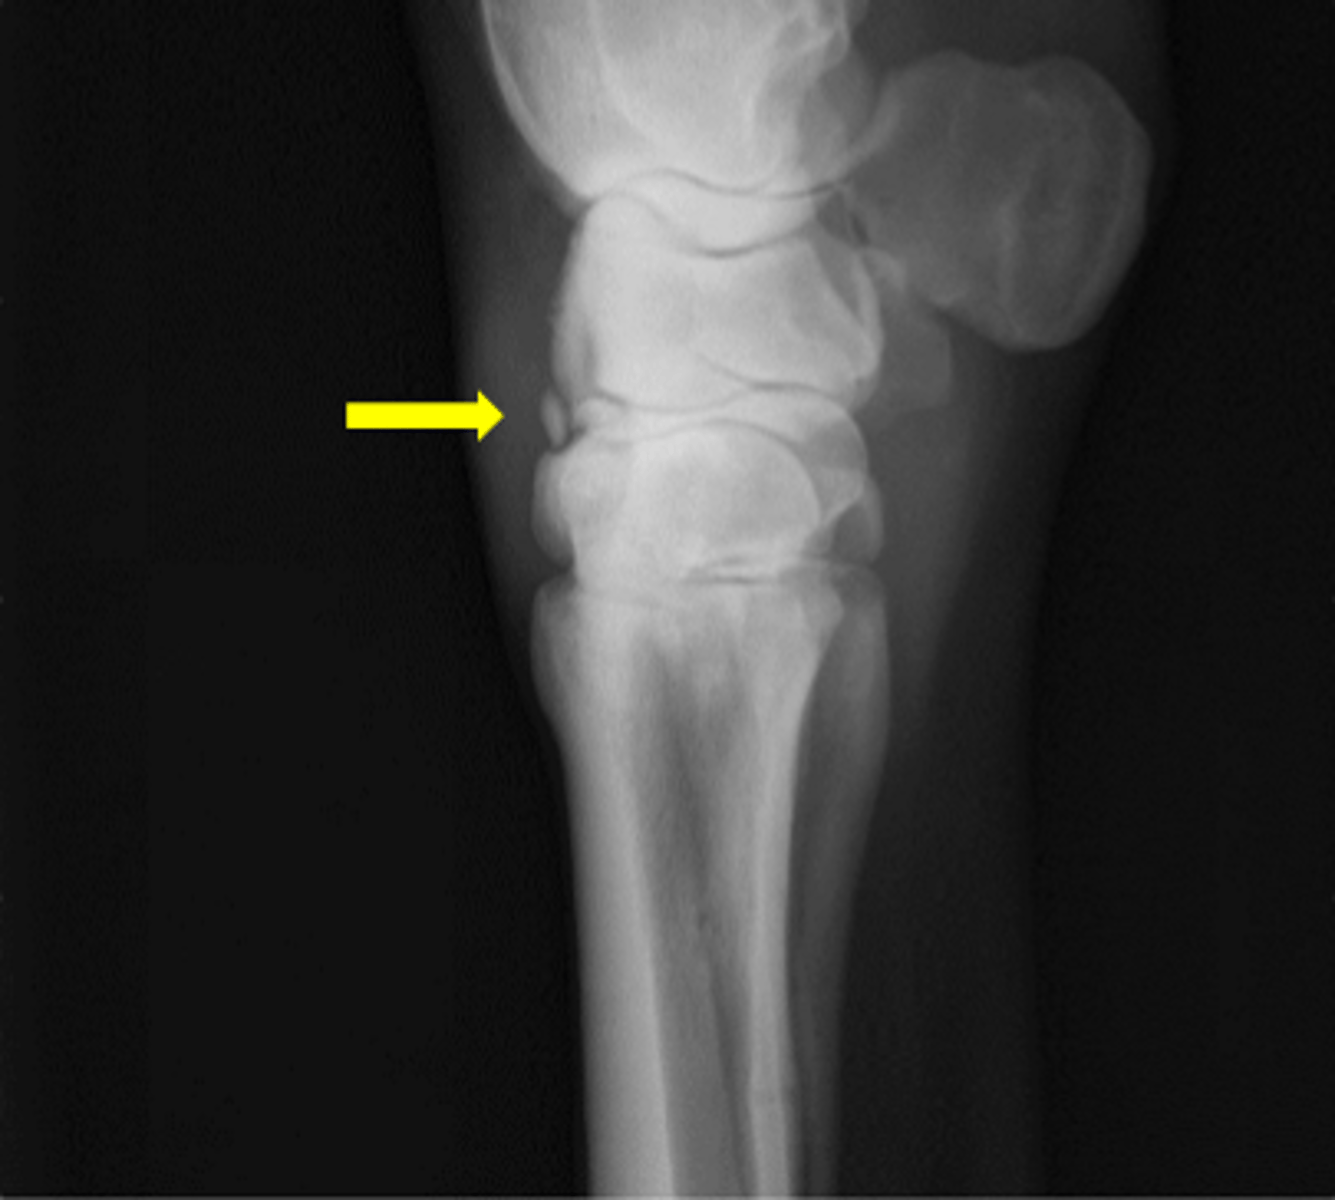

Osteochondral fragment

What is the radiology term for this lesion?

Arthroscopy

What is the preferred treatment for this lesion?